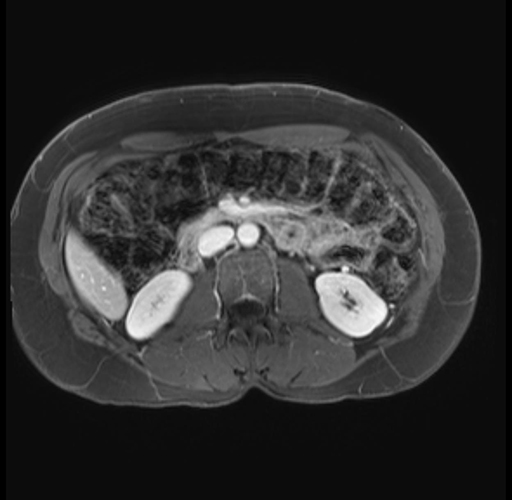

Imaging Analysis

Look through the patient's CT scan to identify any areas of concern for the necessary procedure.

Based on your CT findings, which issue(s) are present and would give reason for "planned slowing down moment(s)" in this case?